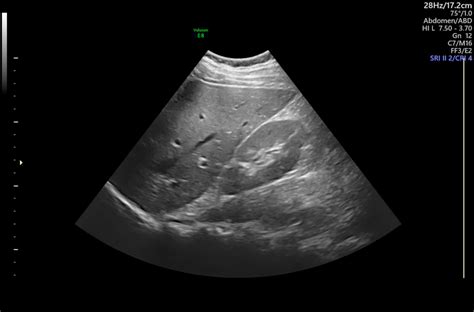

Because ultrasound provides dynamic, real-time visualization of anatomical structures, it has become an indispensable tool for radiologists and sonographers. Whether checking a developing fetus during pregnancy, investigating abdominal pain, or guiding a needle for a biopsy, ultrasound allows physicians to see what is happening inside the body instantly, making it a critical aspect of modern diagnostic radiology.

• Abdominal Ultrasound: Used to examine the liver, gallbladder, spleen, pancreas, and kidneys for stones, cysts, or masses.